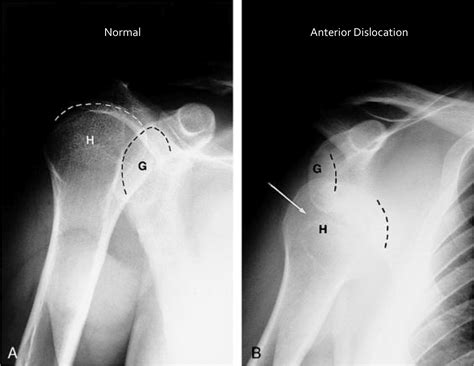

Diagnosing posterior shoulder dislocation involves a combination of physical examination and imaging tests. The diagnostic process typically includes:

• Physical Examination: A healthcare provider will assess the shoulder for deformity, swelling, and range of motion.

• Imaging Tests: X-rays are the primary imaging tool used to confirm the diagnosis. Additional tests such as CT scans or MRIs may be ordered to evaluate the extent of the injury and any associated damage to surrounding tissues.